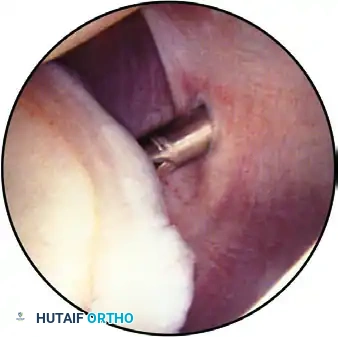

Step 4: The Rotator Cuff Undersurface

The arthroscope is withdrawn slightly to examine the superior capsule and the undersurface of the rotator cuff. The lens is directed superiorly, and the cuff insertion into the greater tuberosity is evaluated while the arm is gently rotated.

Evaluation of the rotator cuff for fraying, partial tears, or calcific deposits. The supraspinatus tendon is visible superiorly, with the biceps tendon in the center.

The arthroscope follows the tendon medially. A semicircular ridge of fibers just medial to the tuberosity insertion is the "rotator cuff arch," a normal anatomical finding.

Surgical Technique - Marking Partial Tears:

When an undersurface partial articular-sided tendon avulsion (PASTA) is identified, its depth is probed. The area is marked by passing an 18-gauge spinal needle through the tear from a lateral approach, deploying a polydioxanone (PDS) suture. This allows the surgeon to locate the exact site of the lesion when viewing from the subacromial space later in the procedure. Minor fraying can be treated with light motorized debridement to stimulate a localized healing response.